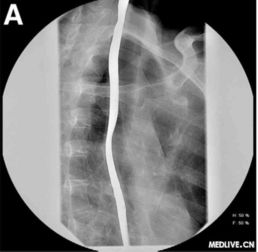

為了保證檢查準確,做食道鋇餐檢查早晨不能吃飯喝水,包括肝功,血脂,血糖等檢查也是這樣要求的.X線鋇餐檢查 食管X線鋇餐檢查可顯示鋇劑在癌腫點停滯,病變段鋇流細窄;食管壁僵硬,蠕動減弱,粘膜紋變粗而紊亂,邊緣毛糙;食管腔狹窄而不規(guī)則,梗阻上段輕度擴張,并可有潰瘍壁龕及棄盈缺損等改變。

常規(guī)X線鋇餐檢查常不易發(fā)現(xiàn)淺表和小癌腫。應(yīng)用甲基纖維素鈉(sodium methyl cellulose)和鋇劑作雙重對比造影,可更清楚地顯示食管粘膜,提高食管癌的發(fā)現(xiàn)率。